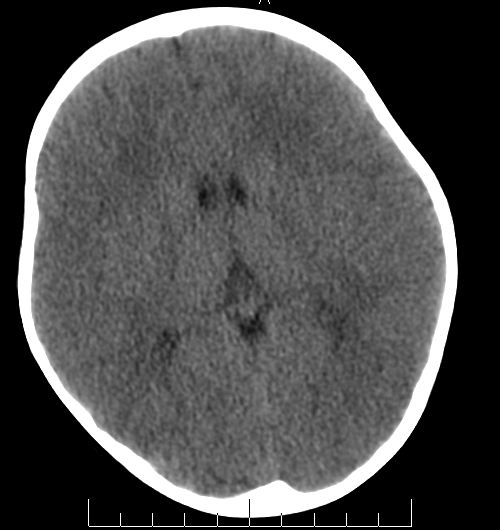

女,3岁,头部外伤一小时。半卵圆中心低密度是什么意思,病灶?侧脑室?请指教。

正常表现

脑白质

考虑为低密度病灶!建议增强或核磁!

幼儿正常脑白质表现,长期观察,必要时mr

从层面看不是侧脑室,考虑低密度变,建议mri。

不是侧脑室,考虑正常脑白质。为慎重,建议mr!